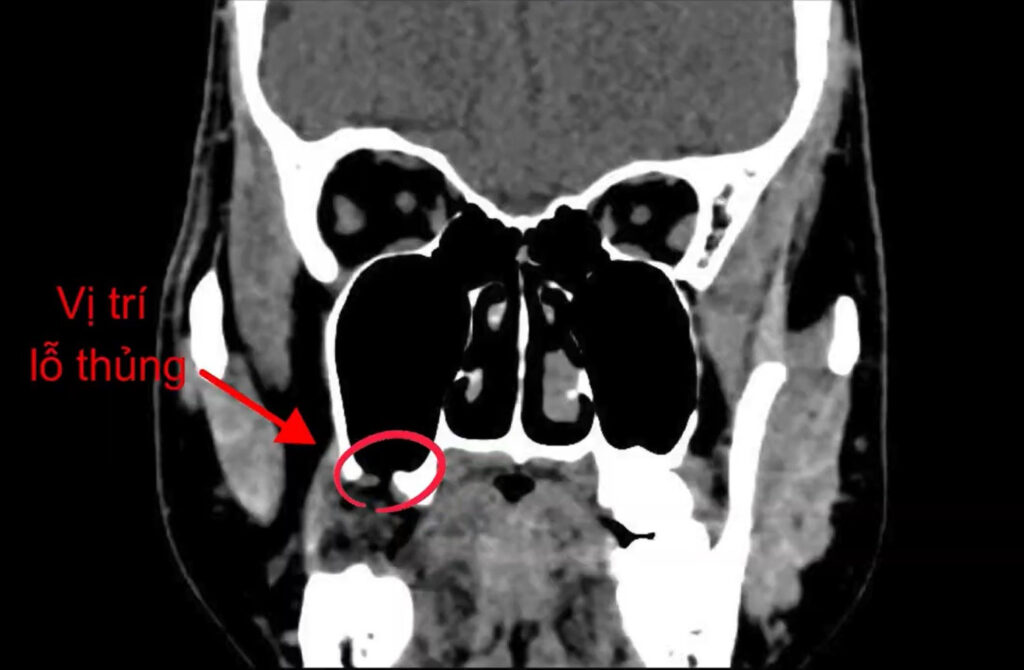

Về bản chất, thủng xoang hàm là sự phá vỡ rào cản ngăn cách giữa hốc miệng (nhiều vi khuẩn) và xoang hàm (vô trùng), tạo điều kiện cho vi khuẩn xâm nhập gây viêm nhiễm nghiêm trọng.

Để hiểu rõ thủng xoang hàm là gì, chúng ta cần hình dung cấu trúc giải phẫu. Xoang hàm được lót bởi một lớp màng mỏng gọi là màng Schneiderian. Lớp màng này có nhiệm vụ duy trì độ ẩm và làm sạch không khí khi chúng ta hít thở. Phía dưới xoang hàm là xương hàm trên, nơi nâng đỡ các răng hàm số 5, 6, 7 và răng khôn (số 8).

Khi có một lực tác động cơ học mạnh hoặc do tình trạng viêm nhiễm làm tiêu hủy lớp xương mỏng ngăn cách này, màng xoang sẽ bị rách. Kết quả là tạo thành một “con đường thông thương” nối giữa miệng và xoang. Điều này cực kỳ nguy hiểm vì môi trường miệng chứa hàng tỷ vi khuẩn, thức ăn và nước bọt. Khi chúng xâm nhập vào xoang qua lỗ thủng, xoang sẽ bị nhiễm trùng ngay lập tức, dẫn đến viêm xoang hàm do răng.

Chân răng hàm lớn hàm trên (đặc biệt là răng số 6 và số 7) thường có 3 chân, trong đó chân trong thường hướng thẳng vào xoang hàm. Nếu chiếc răng này bị sâu nặng hoặc bị viêm quanh chóp, vi khuẩn sẽ làm tiêu hủy lớp xương ngăn cách chân răng và xoang. Khi bác sĩ thực hiện thao tác nhổ bằng lực bẩy, phần chân răng hoặc một mảnh xương ổ răng có thể bị đẩy ngược vào trong lòng xoang, gây rách màng xoang và tạo ra lỗ thủng.